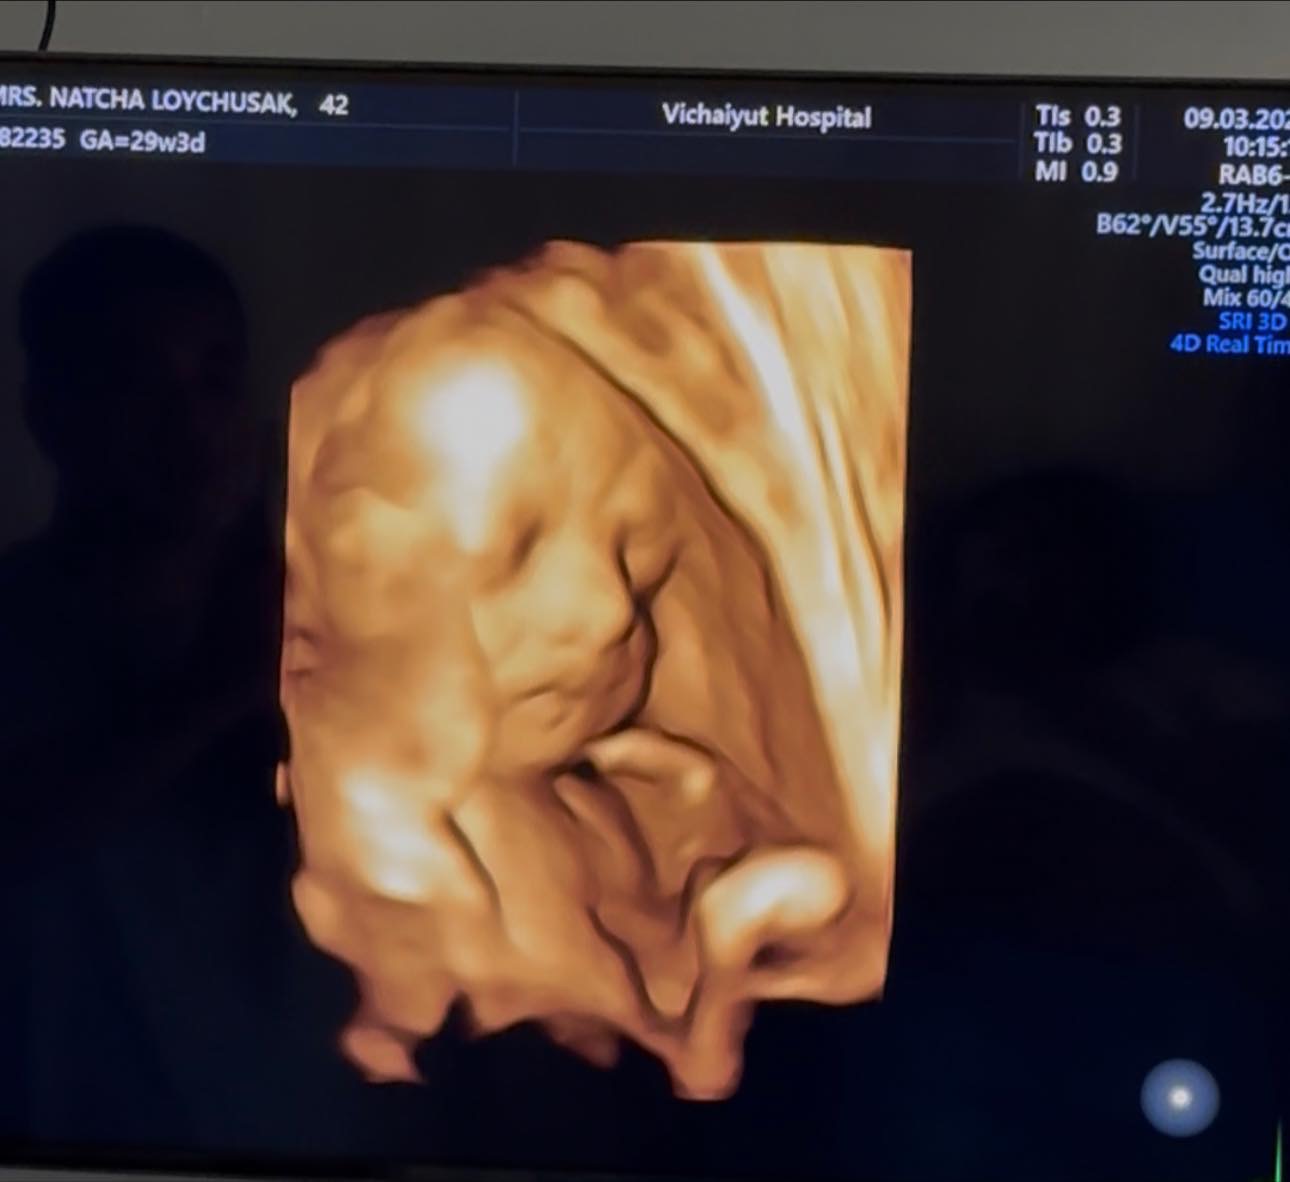

ล่าสุดครูก้อยได้ออกมาอัปเดตพัฒนาการของลูกน้อยในครรภ์ “น้องมีเมตตา” หลังเข้าพบแพทย์ตามนัด พร้อมอัลตราซาวด์ตรวจสุขภาพ โดยระบุว่าขณะนี้การตั้งครรภ์กำลังเข้าสู่ ช่วงไตรมาสสุดท้าย

โดยครูก้อยเผยว่า ขณะนี้อายุครรภ์อยู่ที่ 29 สัปดาห์ และข่าวดีคือ “น้องมีเมตตากลับหัวเรียบร้อยแล้ว” ซึ่งถือเป็นสัญญาณที่ดีของการเตรียมตัวเข้าสู่ช่วงโค้งสุดท้ายของการตั้งครรภ์

ผลตรวจจากแพทย์ระบุว่า น้ำหนักเบบี๋ 1,356 กรัม อยู่ในเกณฑ์มาตรฐาน ปริมาณน้ำคร่ำดี รกเกาะตำแหน่งปกติ และการไหลเวียนเลือดไปเลี้ยงสายสะดือดี โดยภาพรวมแพทย์ประเมินว่า สุขภาพของทารกในครรภ์แข็งแรงสมบูรณ์ดี

ขณะที่คุณพ่ออย่าง เจมส์ เรืองศักดิ์ ก็ได้โพสต์ผ่านเฟซบุ๊ก Raungsak James Loychusak อัปเดตภาพอัลตราซาวด์ของลูกสาวคนที่สอง “น้องมีเมตตา” ที่กำลังเติบโตแข็งแรงในครรภ์ พร้อมข้อความที่ทำเอาแฟน ๆ ยิ้มตาม

“น้องมีเมตตา ในวัย 29 สัปดาห์ 4 วัน พัฒนาการดีตามเกณฑ์ น้องกลับหัวแล้ว ดูทรงท่าจะขี้อ้อนปะป๊าเหมือนพี่สาวเธอแน่ ๆ ปะป๊าเตรียมใจละลายอีกคูณสอง”